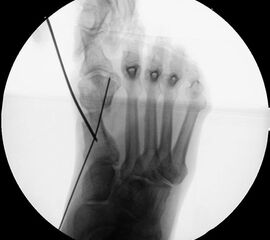

Präoperatives Röntgenbild Fuß d.p. mit eingezeichneten Winkeln. A) Intermetatarsalwinkel, B) Hallux valgus Winkel, C) Interphalangeal-Winkel.

Abbildung 2

• Operationsplanung anhand der Röntgenaufnahmen unter Beachtung wichtiger radiologischer Landmarks wie Intermetatarsalwinkel, Hallux valgus – Winkel, distaler Gelenkflächenwinkel (Distal Metatarsal Articular Angulation - DMAA), Metatarsaleindex und Sesambeinposition (Abb. 2).